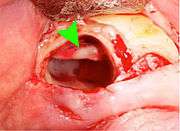

Coronectomy

Coronectomy is a procedure used when the surgeon believes that there is a high risk of inferior alveolar nerve injury. After making the incision in the mucosa and removing bone adjacent the tooth, the crown is cut and removed with no attempt at removing the roots. It is indicated when there is no disease of the dental pulp or infection around the crown of the tooth and there is a high risk of inferior alveolar nerve injury.

Coronectomy, while lessening the immediate risk to the inferior alveolar nerve function has its own complication rates and can result in repeated surgeries. Between 2.3% and 38.3% of roots loosen during the procedure and need to be removed and up to 4.9% of cases require reoperation due to persistent pain, root exposure or persistent infection. The roots have also been reported to migrate in 13.2% to 85.9% of cases.[27]